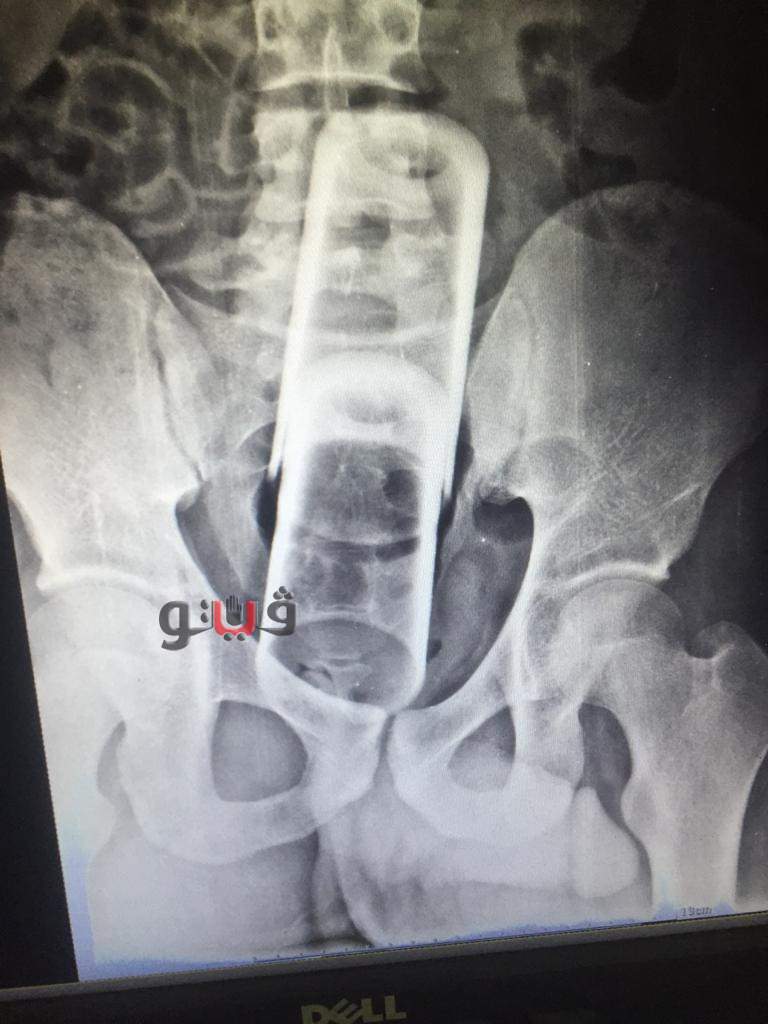

نجح فريق طبي في مستشفى المنصورة التخصصي بمحافظة الدقهلية في استخراج كوبين زجاجيين من قولون شاب عشريني.

وفي حادث غريب ادعى العشريني سقوطه على جسم غريب صلب وبفحص المريض تبين وجود كوبين زجاجيين بالقولون.

ومن جانبه صرح الدكتور فهمي السعيد مدير عام مستشفى المنصورة التخصصى بأن عملية استخلاص الجسم الغريب بعد دخوله للقولون عن طريق المستقيم وصعوبة إخراجه من أسفل أدى إلى عمل فتح جراحي للقولون واستخراج الجسم الغريب وعمل فتحة مؤقتة للإخراج وسيتم قفلها وعودة المسار الطبيعي للإخراج بعد عدة أشهر قليلة.